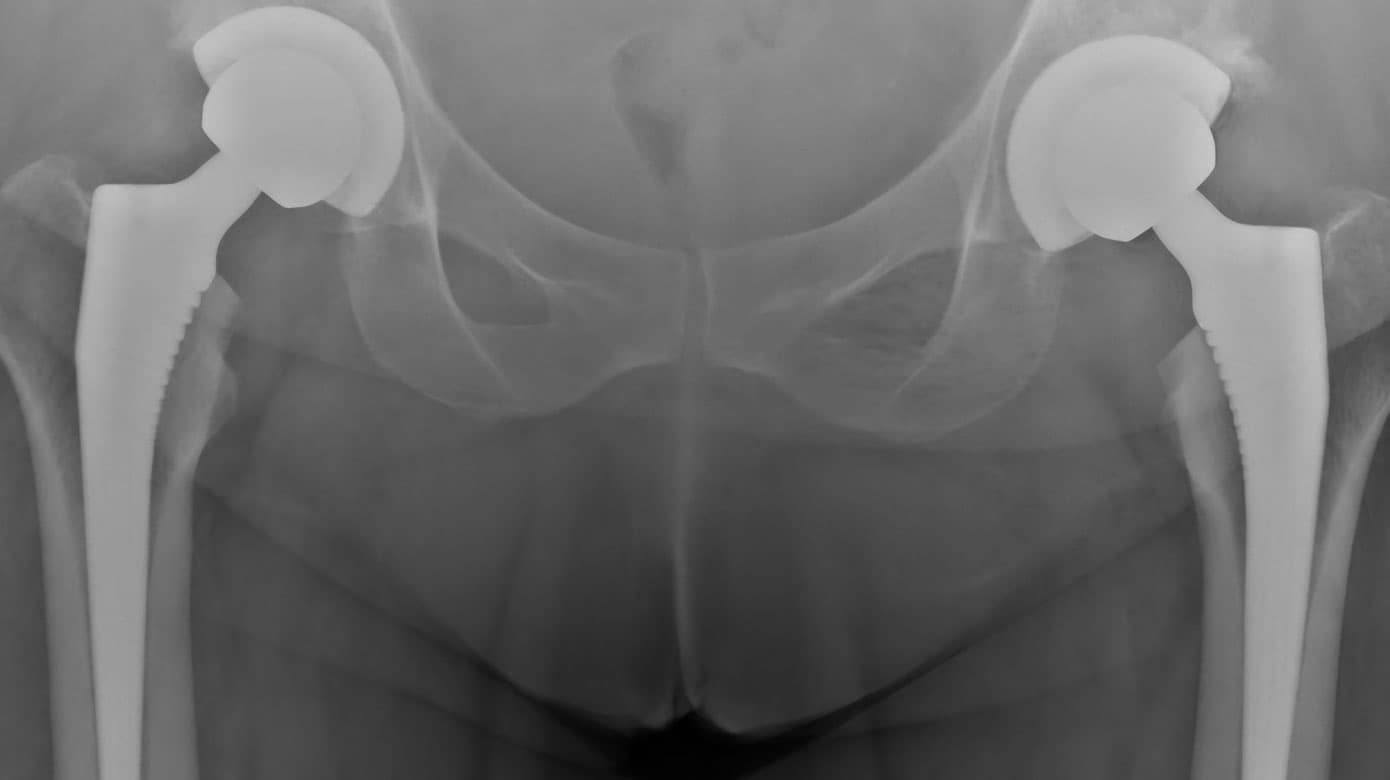

Patienten blev tilbudt bilateral THA med operation ad to omgange. Operationerne blev udført med godt radiologisk resultat (Figur 1 C). Peroperativt blev der fundet PA med skaldannelse af normalt udseende brusk og subkondral knogle med underliggende kollaberet caput femoris, som dermed klinisk understøttede diagnosen ON (Figur 1 D og E).